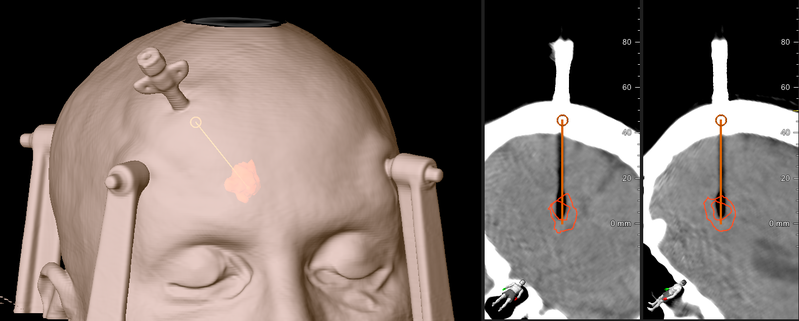

Fil:3Dbolt.png

Oprindelig fil (1.431 × 575 billedpunkter, filstørrelse: 491 KB, MIME-type: image/png)